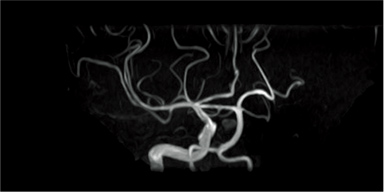

Subtraction of images with and without BeamSat pulses can be displayed in a reversed black-and-white image to visualize it as in MR-DSA.

Without BeamSat

With BeamSat

Subtraction image (reversed black-and-white image)